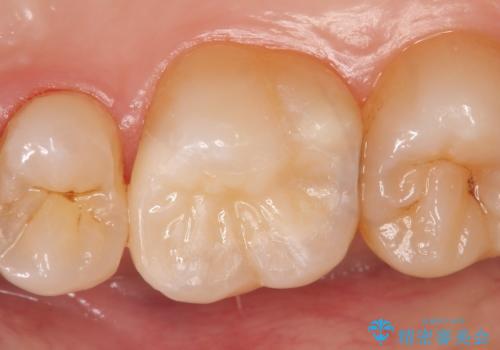

虫歯を除去後、セラミックインレーによる修復を行いました。

当院のセラミックインレーはemaxという強度と審美性に優れた材料を使用しています。

またプレス方式でインレーを製作しているため、削り出しで製作するCADCAMより優れた適合性も持ち合わせており、虫歯が再発しにくい修復物です。